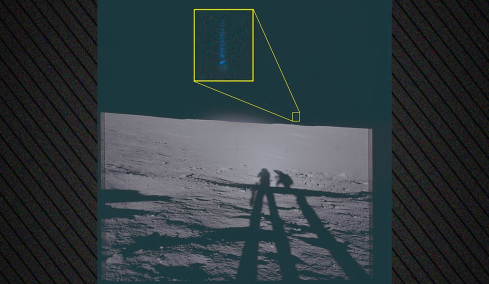

Επιστήμονες στις ΗΠΑ ανακάλυψαν μια νέα μέθοδο, που θυμίζει βιολογική αλχημεία και η οποία επιτρέπει για πρώτη φορά να μετατρέπονται ανοιχτά τραύματα σε νέο υγιές δέρμα.

Η νέα τεχνική -που βρίσκεται σε αρχικό στάδιο ανάπτυξης και ακόμη δεν είναι ώριμη για κλινική αξιοποίηση σε ανθρώπους- καθιστά εφικτό τον απευθείας αναπρογραμματισμό των κυττάρων του τραύματος σε νέα δερματικά κύτταρα.

Όταν τελειοποιηθεί η νέα μέθοδος, μπορεί να καταστήσει περιττή την μεταμόσχευση υγιούς δέρματος μέσω πλαστικής χειρουργικής σε περιπτώσεις όπου υπάρχουν μεγάλα τραύματα π.χ. από σοβαρά εγκαύματα ή από χρόνιες παθήσεις, όπως τα έλκη λόγω διαβήτη. Σήμερα, όταν δεν υπάρχει διαθέσιμο επαρκές υγιές δερματικό μόσχευμα, πρέπει να καλλιεργηθεί εξ αρχής νέος δερματικός ιστός στο εργαστήριο, ώστε μετά να μεταμοσχευθεί, μια διαδικασία που είναι αργή και δαπανηρή.

Οι ερευνητές του Ινστιτούτου Salk της Καλιφόρνια, με επικεφαλής τον καθηγητή Χουάν Κάρλος Ιζπιζούα Μπελμόντε, που έκαναν τη σχετική δημοσίευση στο περιοδικό "Nature", δοκίμασαν με επιτυχία τη μέθοδό τους σε πειραματόζωα (ποντίκια), στα οποία το υγιές δέρμα αναπτύχθηκε στην περιοχή του τραύματος μετά από 18 μέρες. Μετά από λίγους μήνες, το νέο δέρμα δεν διέφερε σε τίποτε από το υγιές δέρμα της γύρω περιοχής.

Ο Μπελμόντε δήλωσε αισιόδοξος ότι με τη νέα τεχνική θα είναι δυνατή η αποκατάσταση τραυμάτων οποιουδήποτε μεγέθους μέσα σε ένα συγκεκριμένο χρονικό διάστημα. Ενώ δεν απέκλεισε ότι ίσως μπορεί να αξιοποιηθεί και σε απλώς γερασμένο δέρμα για να το ξανανιώσει.

Προτού όμως η μέθοδος δοκιμασθεί κλινικά σε ανθρώπους, θα προηγηθούν περισσότερες μελέτες σε ζώα για λόγους ασφαλείας. Η νέα μέθοδος θα δοκιμασθεί επίσης σε άλλους ιστούς και όργανα πέρα από το δέρμα.